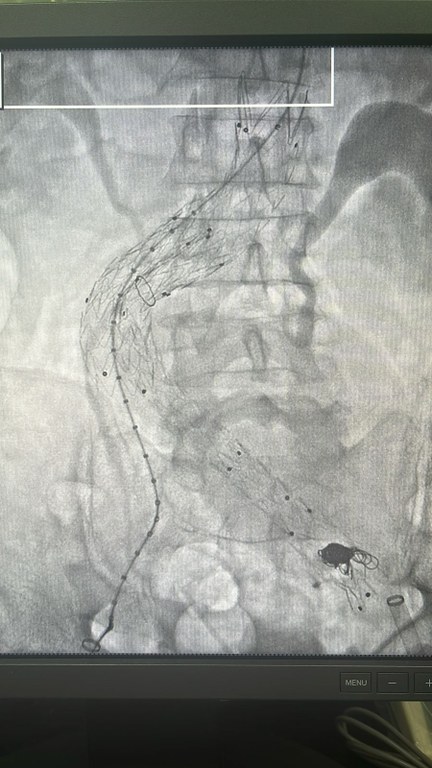

De acordo com o cirurgião Eduardo Roso, a técnica endovascular com Endoprótese aórtico-ilíaca (tubo expansível que faz com que o sangue deixe de circular pela bolsa formada pelo aneurisma) foi combinada com a técnica de embolização (obstrução) da artéria interna esquerda e ocorreu de forma menos invasiva. “Com apenas pequenas incisões na coxa do paciente, foi possível realizar todo o procedimento, proporcionando menores riscos e uma alta hospitalar precoce”, pontuou.